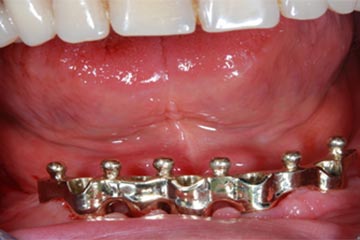

I denti irrecuperabili dell'arcata superiore ed inferiore del paziente di anni 65

sono stati sostituiti da 10 impianti, cioè protesi radicolari endo-ossee che sostengono le protesi fisse superiore ed inferiore.